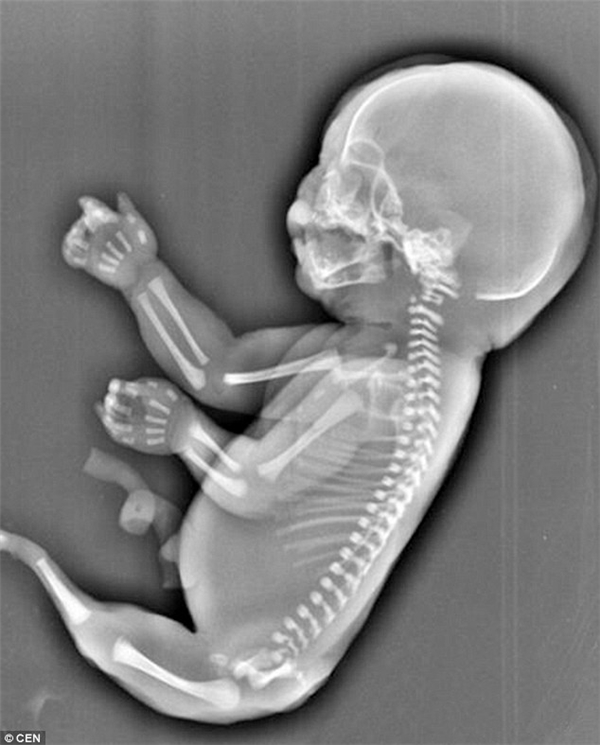

Hội chứng nàng tiên cá hay còn gọi là hội chứng người cá (hội chứng Mermaid) là một rối loạn phát triển bẩm sinh cực kỳ hiếm gặp.

Trẻ sơ sinh bị ảnh hưởng sinh ra với hai chân hợp lại một phần hoặc toàn bộ. Các dị tật khác kèm theo cũng có thể xảy ra bao gồm các bất thường ở đường sinh dục tiết niệu, các bất thường ở đường tiêu hóa, dị tật cột sống thắt lưng, xương chậu và không có hoặc kém phát triển của một hoặc cả hai thận.

Hội chứng Mermaid là một căn bệnh quái ác từ khi còn nằm trong bào thai. Ảnh minh họa

Trẻ sơ sinh bị hội chứng này có thể có một bàn chân, không có bàn chân hoặc cả hai bàn chân bị xoay ra bên ngoài. Trẻ thường không có xương cụt, xương cùng có thể có một phần hoặc không có. Các tình trạng khác có thể xảy ra với hội chứng người cá như hậu môn bị tịt, nứt đốt sống và các dị tật tim.